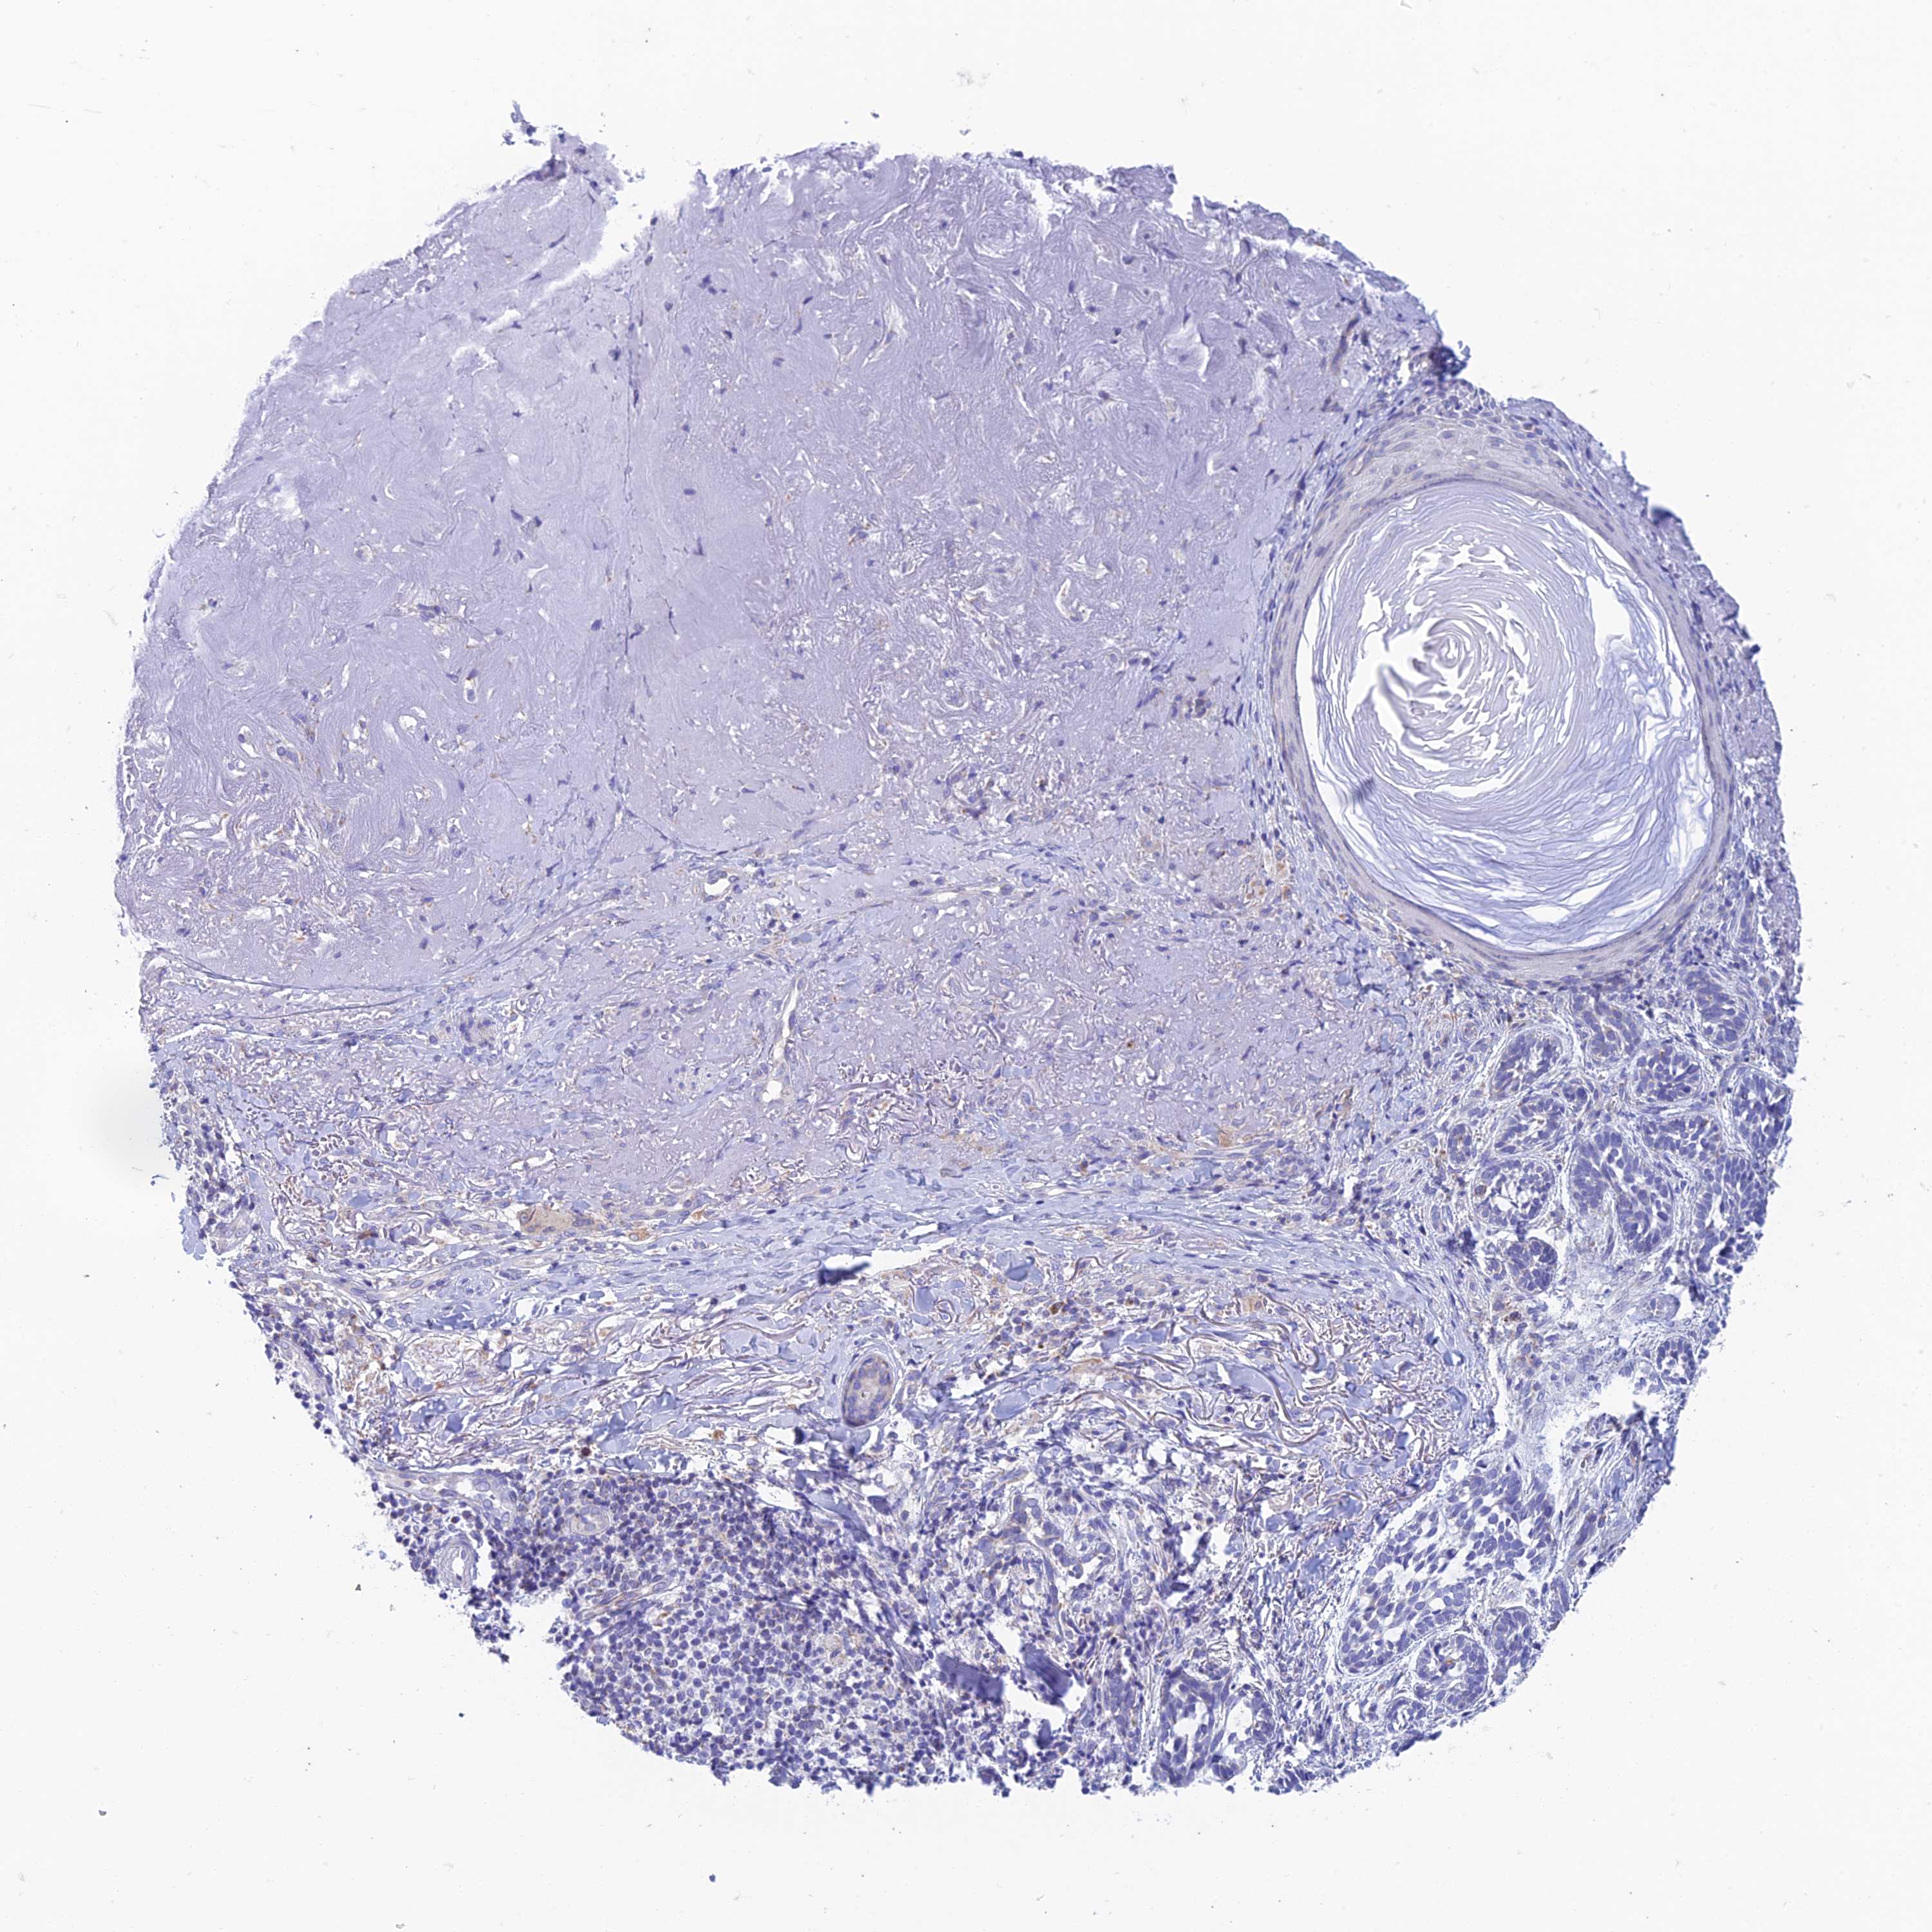

SKIN CANCER - Protein expressioni

A mouse-over function shows sample information and annotation data. Click on an image to view it in a full screen mode. Samples can be filtered based on level of antibody staining by selecting one or several of the following categories: high, medium, low and not detected. The assay and annotation is described here.

Each image is clickable and will lead to virtual microscopy that enables deeper exploration of all samples and also displays staining intensity scores, fraction scores and subcellular localization as well as patient and tissue information for each sample.

Antibody HPA043701

Basal cell carcinoma